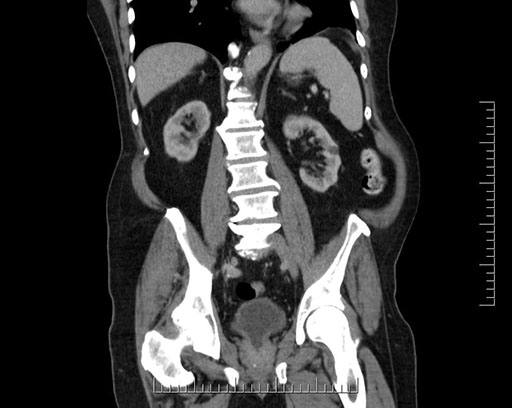

Coronal - stented

Imaging analysis

Based on your CT findings, which issue(s) would give reason for "planned slowing down moment(s)" in this case?

Considering a standard Whipple procedure, what step(s) of the operation would you do differently in this case?